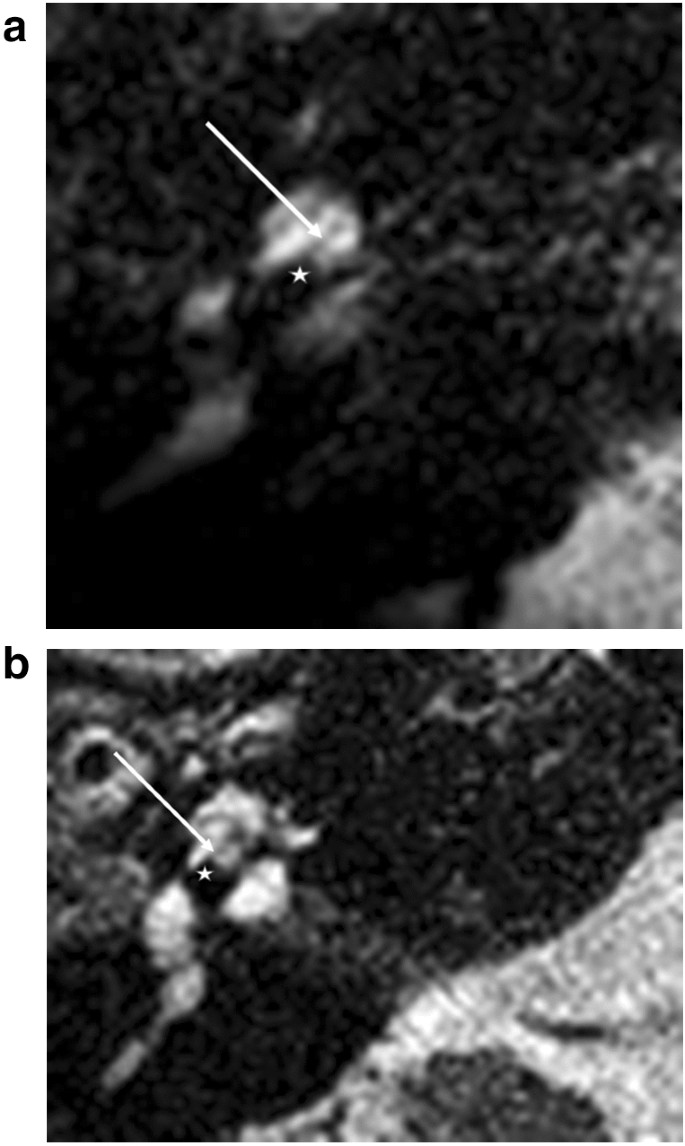

For the basal turn, a diminishing signal indicates the electrode localisation. At the lateral portion of the cochlea, each electrode was positioned depending on its design: either laterally, without any further lateral T2 signal (Fig. 1a,b), or more medially positioned with a T2 signal (Fig. 3). Lateral diminishing signal varied depending on electrode design: Flex 28 was round, and SlimJ laterally flatter. As a second indicator, a basilar membrane was visible. This basilar membrane diminishing signal allowed definitive estimation of the electrode location in the scala tympani or scala vestibuli.

At the first turn, a design-specific difference of the diminishing signal of the electrodes was obvious. We were able to differentiate between a round signal diminishing and a flatter signal diminishing (Fig. 2a,b). The basilar membrane signal (Fig. 2a,b) and the localization of the fluid signal diminishing indicate scala tympani positions at the first turn for these two types of lateral wall electrodes.